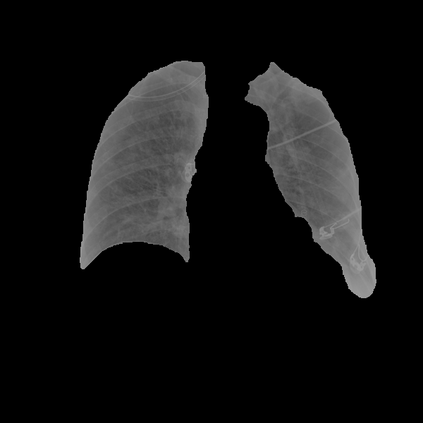

Deep learning technologies have already demonstrated a high potential to build diagnosis support systems from medical imaging data, such as Chest X-Ray images. However, the shortage of labeled data in the medical field represents one key obstacle to narrow down the performance gap with respect to applications in other image domains. In this work, we investigate the benefits of a curricular Self-Supervised Learning (SSL) pretraining scheme with respect to fully-supervised training regimes for pneumonia recognition on Chest X-Ray images of Covid-19 patients. We show that curricular SSL pretraining, which leverages unlabeled data, outperforms models trained from scratch, or pretrained on ImageNet, indicating the potential of performance gains by SSL pretraining on massive unlabeled datasets. Finally, we demonstrate that top-performing SSLpretrained models show a higher degree of attention in the lung regions, embodying models that may be more robust to possible external confounding factors in the training datasets, identified by previous works.